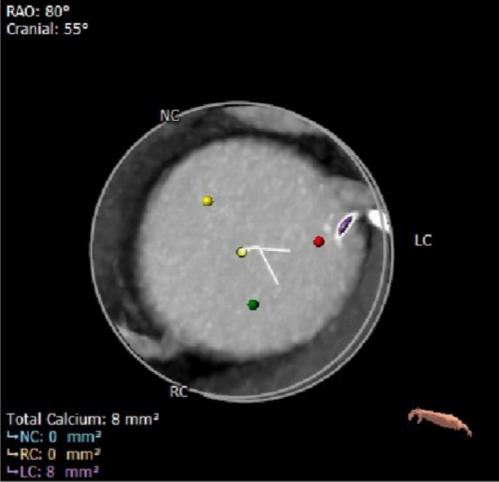

钙化分布: